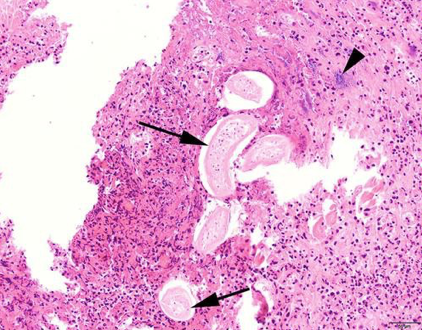

This histology slide contains which equine parasite?

Habronema sp.